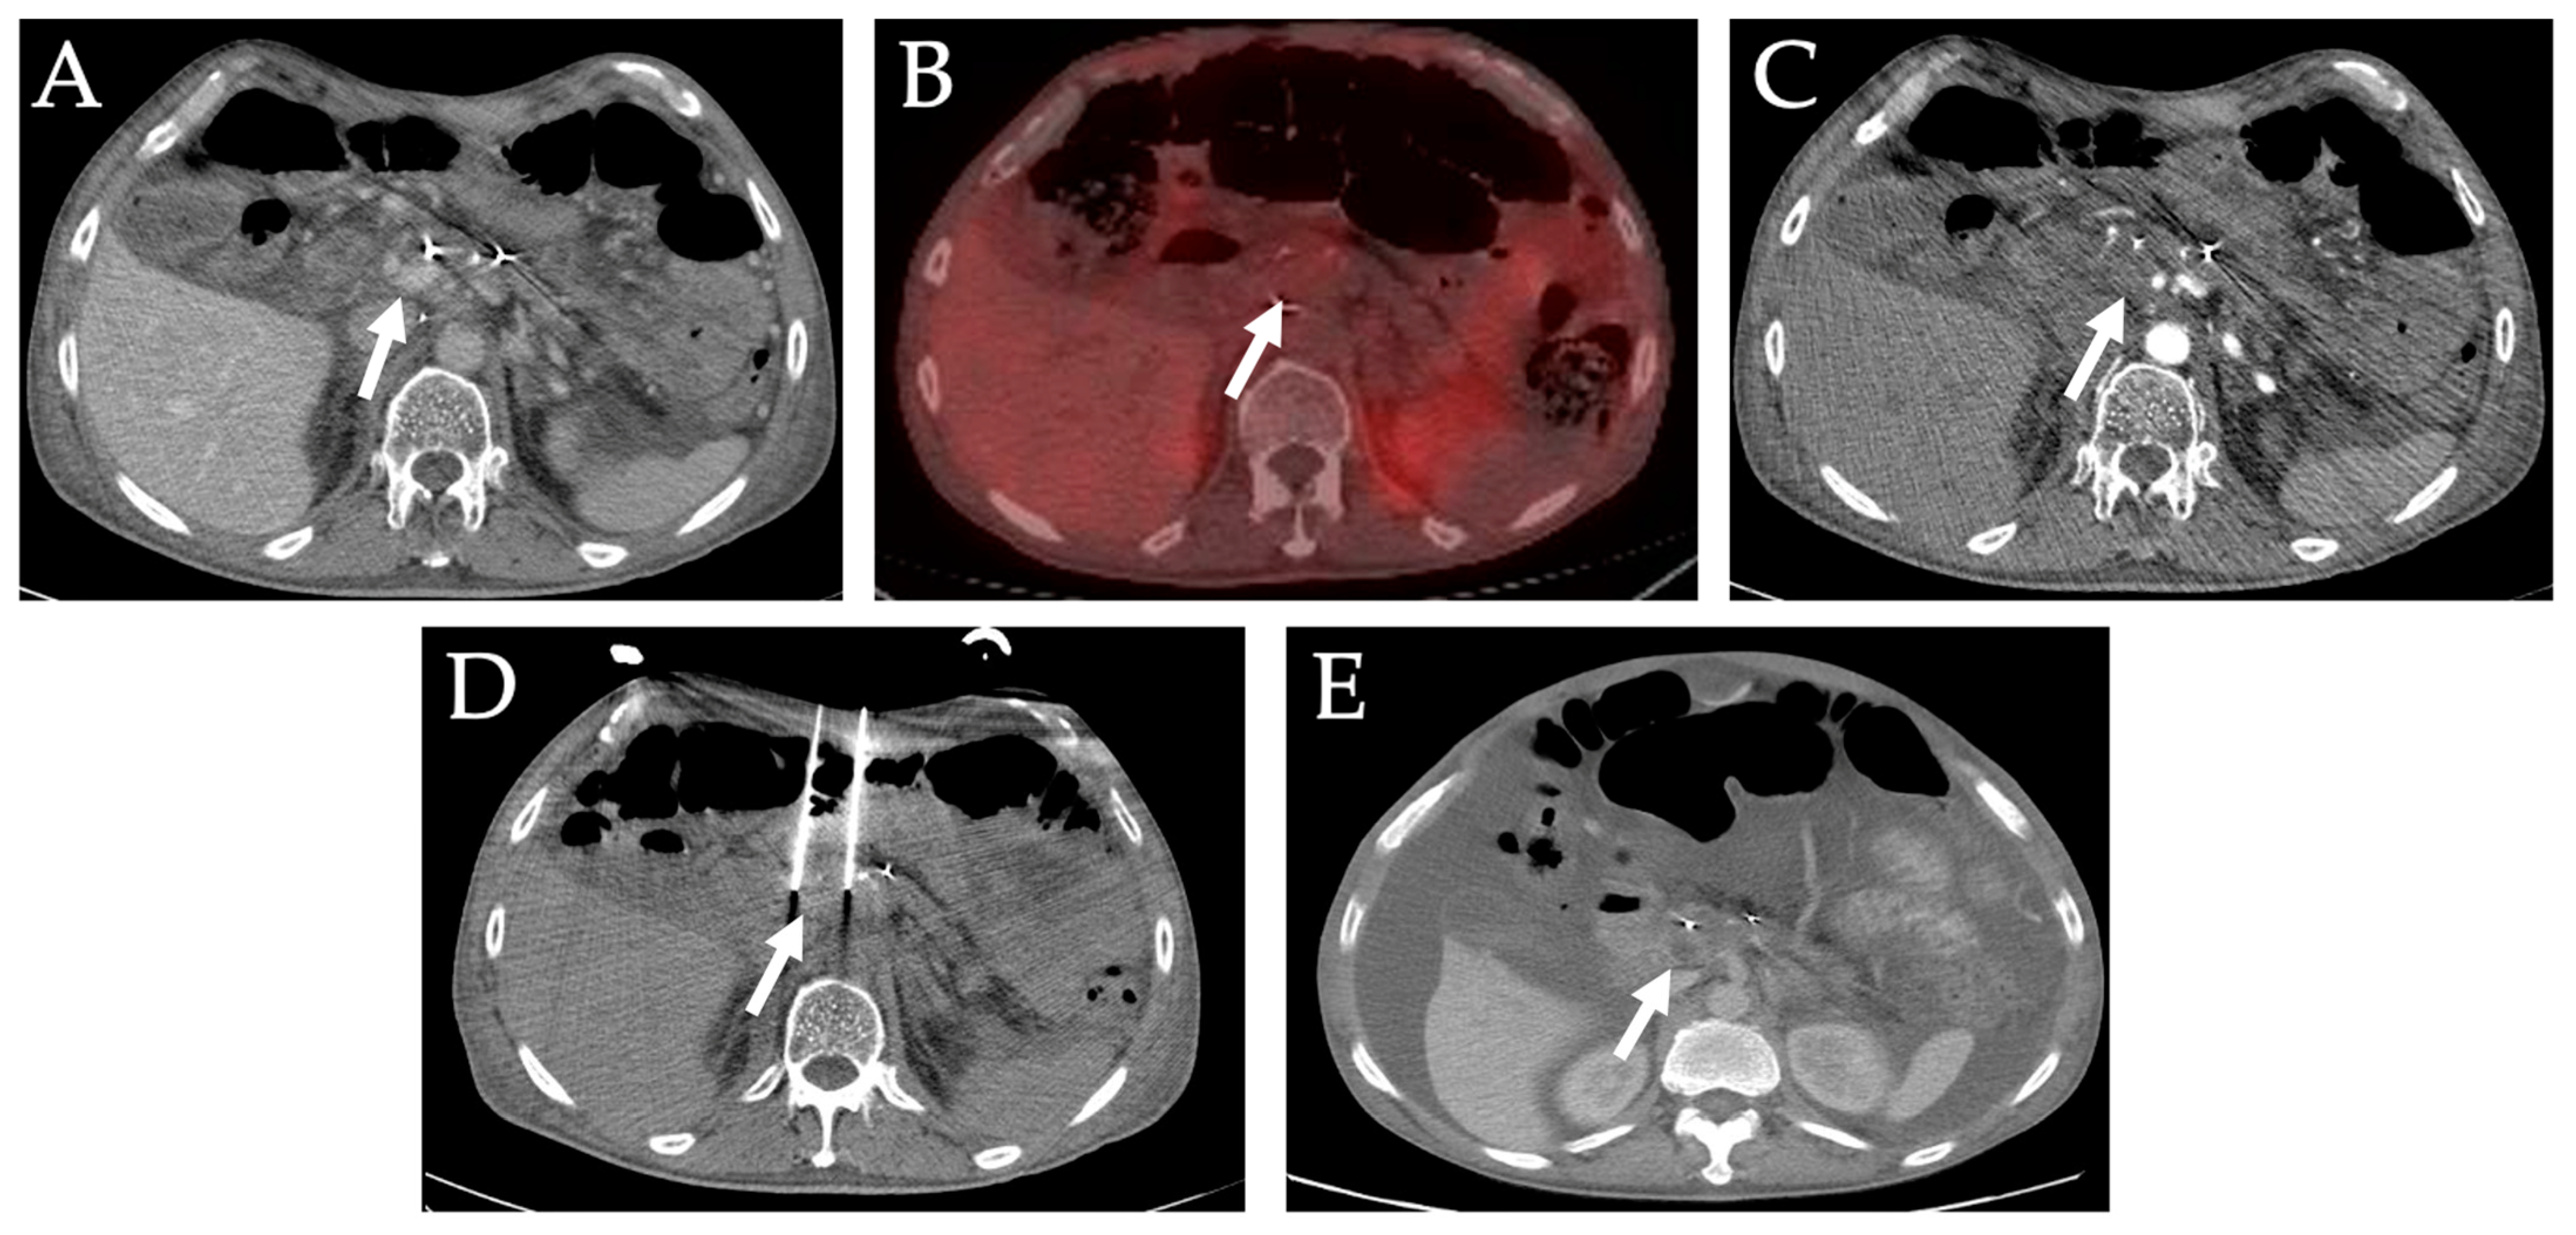

Diagnostics Free Full Text Image Guided Percutaneous Ablation For Primary And Metastatic Tumors